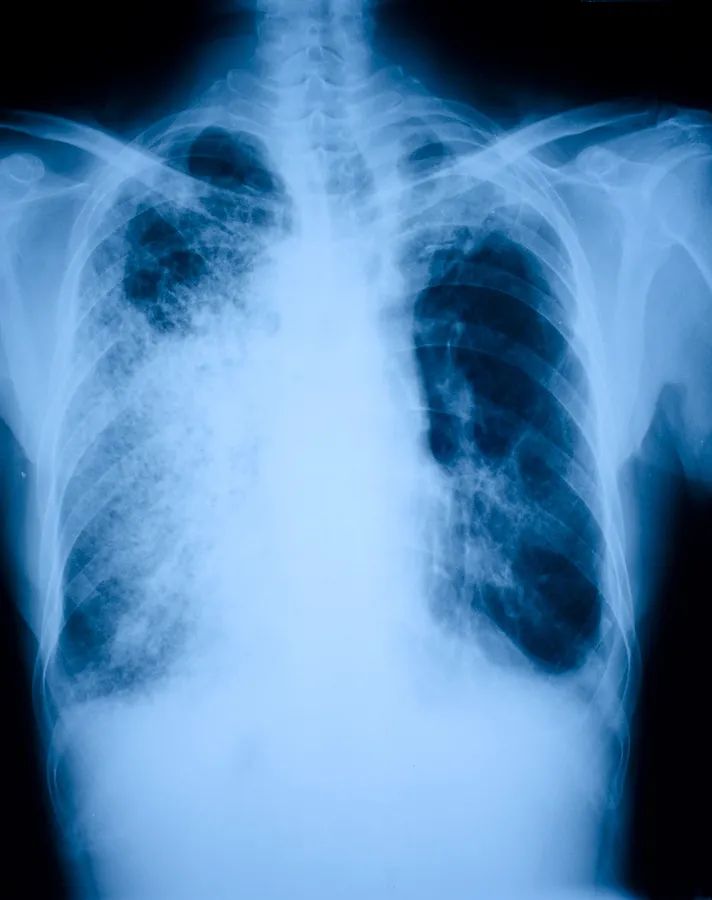

肺炎导致原本柔软且富弹性的肺变得坚硬、失去弹性

肺炎是指肺组织中实质的炎症,绝大多数肺炎几乎都是由感染引起:随着某种微生物侵入肺部,机体会启动抗感染机制,结果由各种细胞、酶、细胞残骸、体液以及瘢痕组织组成的炎症混合物逐渐增厚并导致肺部发生实变。原本柔软、多孔且富弹性的肺变得坚硬、紧密、失去弹性。

一旦肺部出现大面积实变,就不再能把氧气输送入血流,病人就会死亡。即使肺炎的病原体只是侵犯了部分肺部,没有影响氧气的交换,但还有一种情况是原本在肺部的细菌通过了肺血管壁进入血流中后就会随血流感染全身,同样造成死亡。